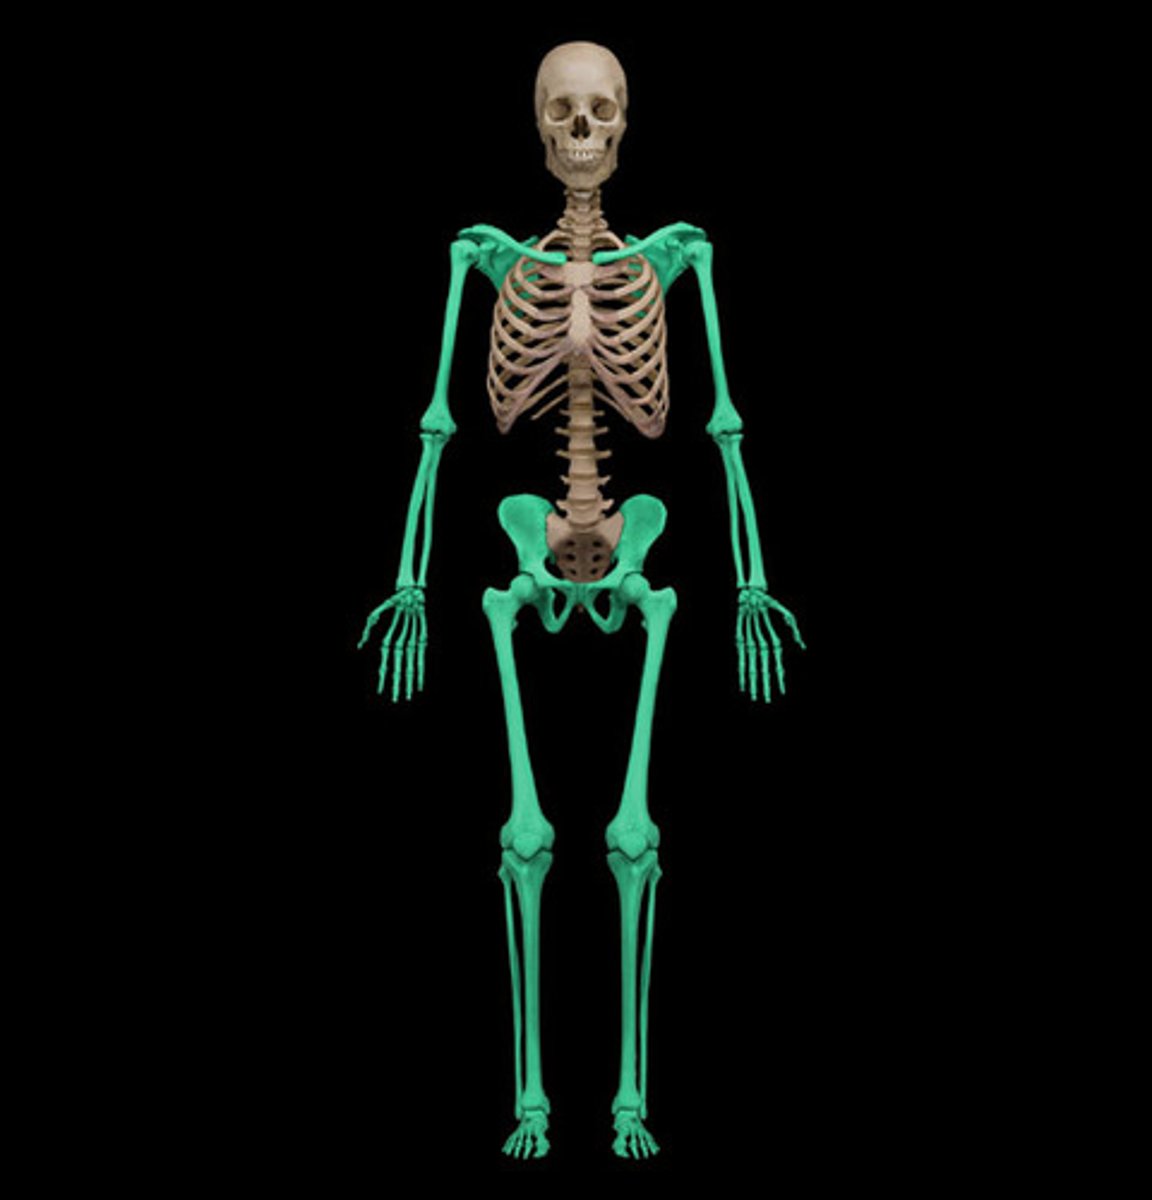

What bones are in the appendicular skeleton

Upper Extremities

-Shoulder (pectorial) girdle

-Arm

-Wrist

-Hands

Lower Extremities

-Hip (pelvic) girdle

-Legs

-Ankles

-Feet

How many bones are in the appendicular skeleton

126 bones